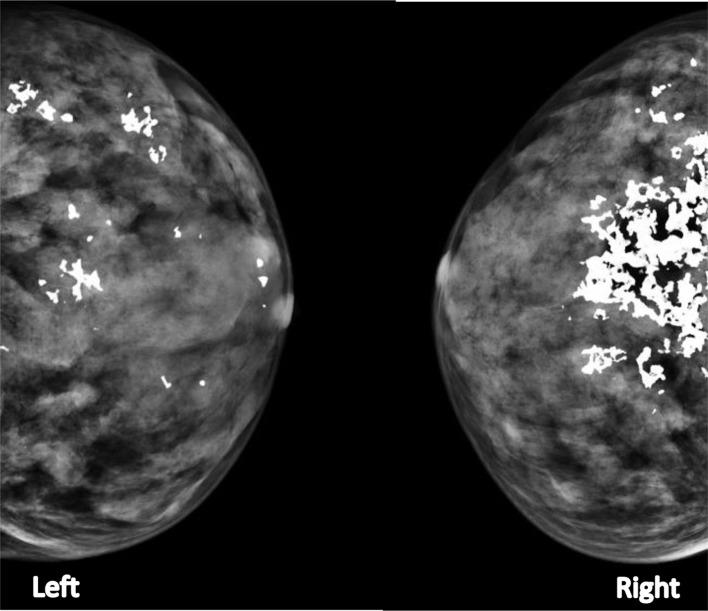

Ochronosis is a syndrome characterized by bluish black discoloration due to the deposition of polymerized products of homogentisic acid (HGA) in the connective tissues. The endogenous variety (alkaptonuria), is a rare autosomal recessive metabolic disorder. The disorder is manifested by deficiency of the enzyme homogentisate 1,2-dioxygenase. The characteristic of the condition is a triad of pigmentation of skin, cartilage, and sclera; ochronotic arthropathies and homogentisic aciduria (resulting in darkening of urine). More rarely, it may affect the breast. This rare and interesting case of a woman with ochronosis of both breasts and chest wall, prompted us to write this case report.

褐黄病是一种综合征,其特征为由于尿黑酸(HGA)的聚合产物在结缔组织中沉积而导致蓝黑色色素沉着。内源性类型(尿黑酸尿症)是一种罕见的常染色体隐性代谢紊乱疾病。该疾病表现为尿黑酸1,2 -双加氧酶缺乏。其特征为皮肤、软骨和巩膜色素沉着、褐黄病性关节病和尿黑酸尿症(导致尿液变黑)三联征。更罕见的是,它可能累及乳房。这位患有双侧乳房和胸壁褐黄病的女性的罕见且有趣的病例促使我们撰写此病例报告。